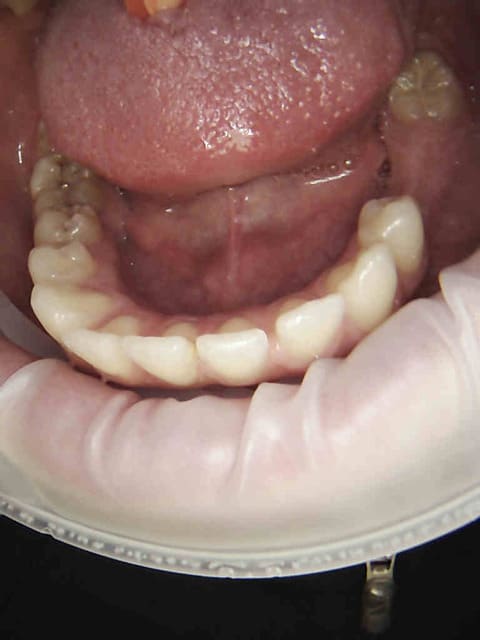

Et merde, encore raté pour les compos à 2 balles sous digue (pas indiqué) raté pour les onlays ceram (pas remboursés) sur 27 et 15 Reste plus que endo-ic-coiffe ou endo-sc33-coiffe en fonction de la mutuelle.))))

1 tf42wf - Eugenol

2 sltqnf - Eugenol

3 qcvnqa - Eugenol